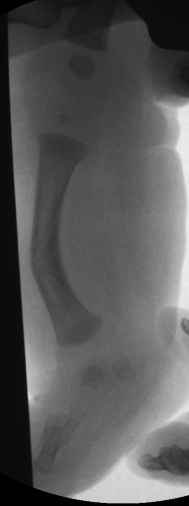

Ув.коллеги, размещаю это сообщение по просьбе друга-коллеги, в надежде услышать любые мнения и замечания по этому случаю. В приложении фото и имеющиеся снимки 3-х месячного мальчика(сейчас ему уже полгода). Родителей интересует буквально все:в какие сроки, где(и у нас в стране, и за рубежом), в какой последовательности надо решать проблему, существуют ли какие то целевые программы, где накоплен наибольший опыт лечения таких детей.. всем откликнувшимся заранее спасибо.